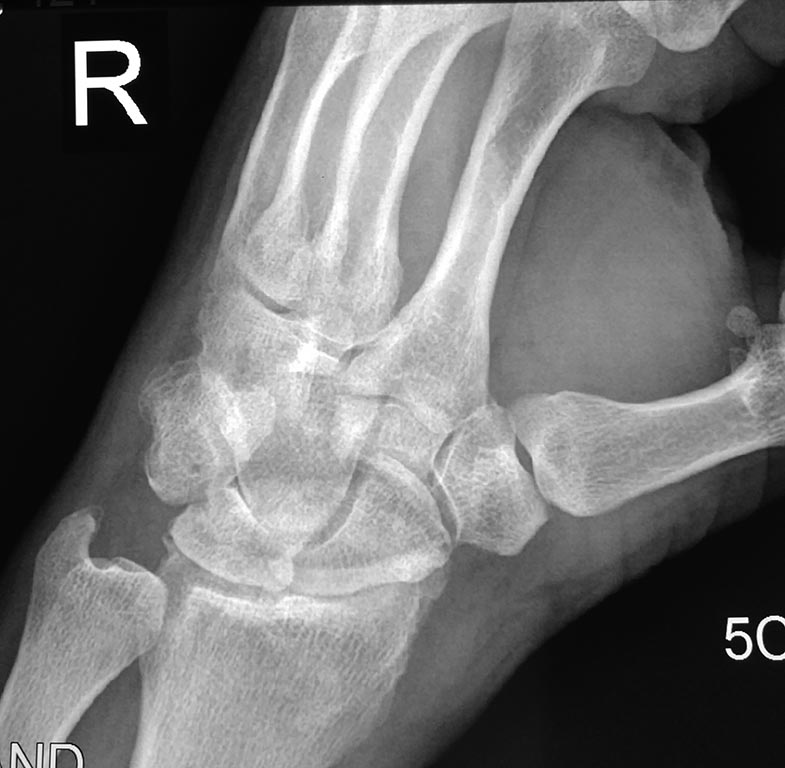

[Ortho] боли в лучезапястном суставе

проекции

Имя     : IMG_20170312_155644.jpg

Тип     : image/jpeg

Url     : http://weborto.net:8080/pipermail/ortho/attachments/20170313/b38b27b5/attachment-0002.jpg